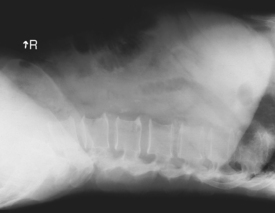

Lateral and dorsal decubitus critique

• Patient supine (on decubitus board or support to elevate posterior abdomen), side against table, arms above head

• Secure stretcher (lock wheels)

• Center of IR and table (and CR) at level of iliac crest (2″ above iliac crest to include diaphragm)

• Adjust height of IR to align midcoronal plane to centerline of IR

• Immobilize arms above head (use stockinette, Ace bandage, tape, or sandbags).